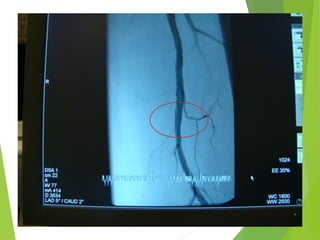

Пациент М., 1940г.р. – критическая ишемия, боли в покое. Начало

заболевания 3 недели назад

Ротационная тромбэктомия, баллонная ангиопластика и стентирование

самораскрывающимся стентом